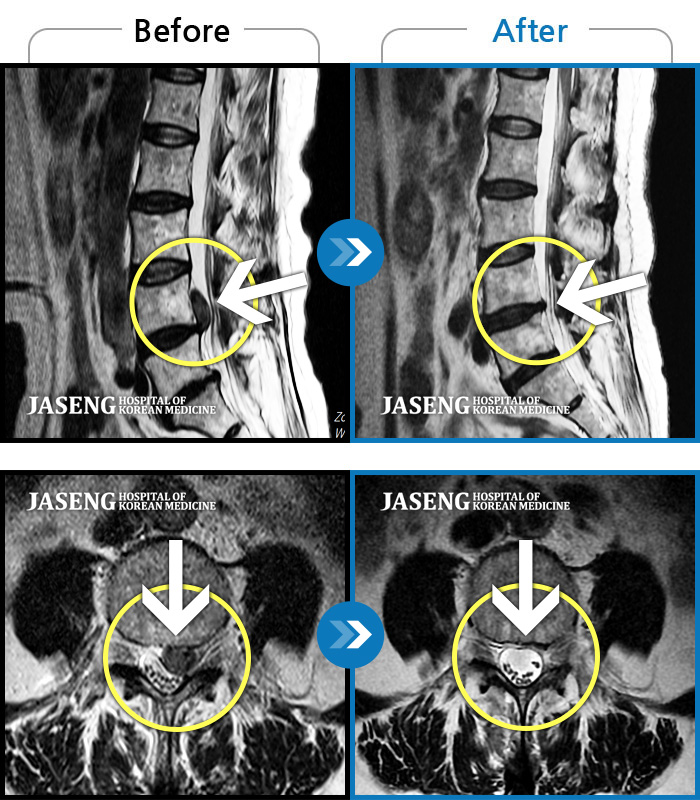

[뱸] 19.11.28~25.05.06

ȯںп Ǹ ǿ ԿǾ, ο ġ ۿ Ƿ ġḦ Ͻñ ٶϴ.